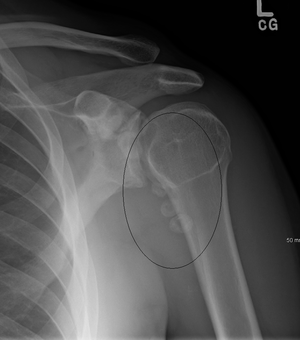

Typical finding is of multiple, smooth, oval-shaped calcified masses within the joint space or bursa. They have a characteristic popcorn-ball appearance of calcified cartilage. With serial imaging, masses may be found to change in size, disappear, or migrate to recessed areas of the joint. They may pass from the main joint cavity into a neighboring synovial cyst. For this reason, a mass may not be appreciated within the actual joint space itself.

Additional radiographic findings include joint effusion and degenerative changes such as joint space narrowing, subchondral sclerosis, and osteophyte formation.

Intra-articular bodies in SOC typically have popcorn calcification, with a dense sclerotic border with radiolucent central region. This distinct radiographic appearance sets it apart from other cause of intra-articular bodies. Number and size of intra-articular bodies can prove helpful as well. SOC typically presents as multiple intra-articular bodies. Few or isolated intra-articular bodies are more consistent with trauma or osteoarthritis.